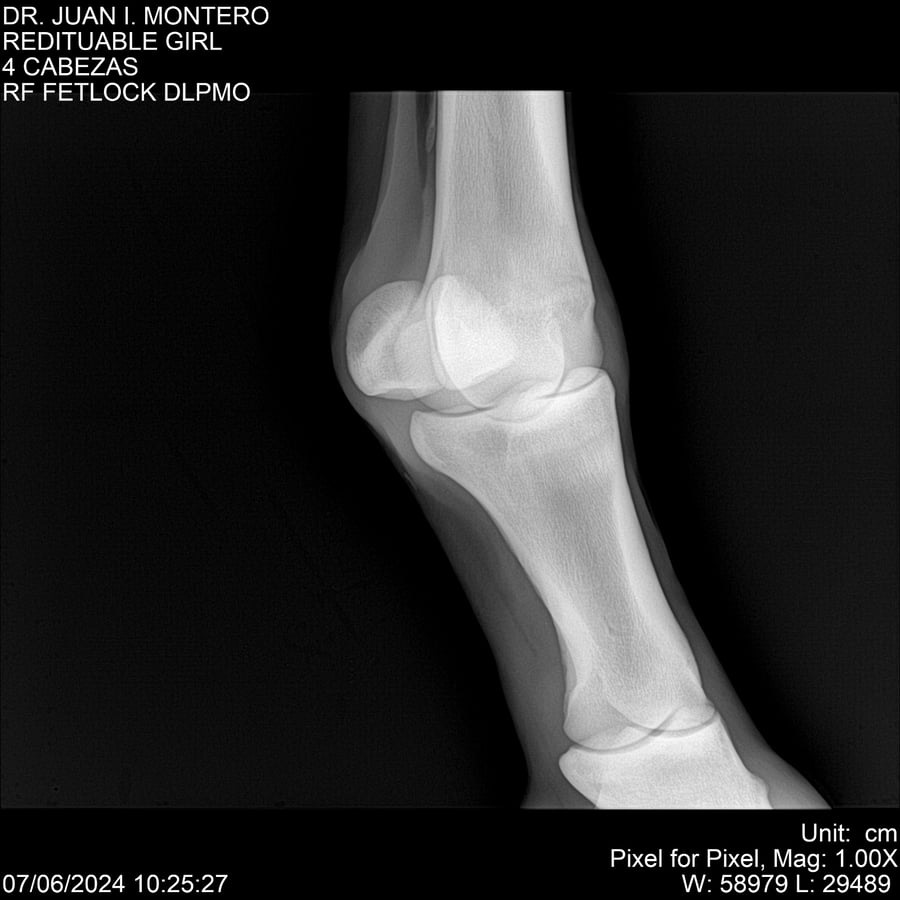

LOTE 19, REDITUABLE GIRL Lote Anterior Volver al remate Lote Siguiente Ficha Contacto Montevideo - Ficha del Lote Identificador: #281096 Categoría: Yeguarizos Montevideo - 79 Visualizaciones ClicData Contacto Empresa: Abelenda N. R., Walter Hugo Nombre*: Teléfono* : E-mail* : Mensaje Enviar Registrese gratis Este contenido Exclusivo está disponible sólo para usuarios registrados Ingresar